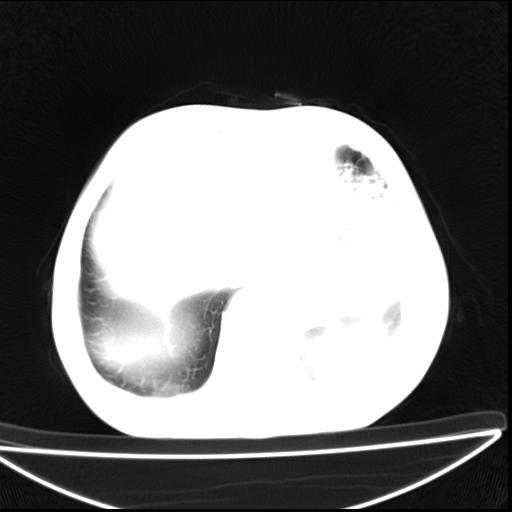

标题: CT27010:男 70岁 左胸廓塌陷,肺TB [打印本页]

男  70岁,发烧咳嗽4天。盗汗,消瘦。无痰中带血丝,以前有肺tb病史,ct见,双肺tb,左侧胸廓塌陷,左胸膜肥厚粘连。纵隔移位,右侧胸腔积液,大家说说那个心影前左肺舌叶除了肺大炮还有炎症还是干酪性肺炎?有占位吗?我看纵隔淋巴结也大。

1)两肺继发性肺结核并左肺上叶肺不张,支气管扩张。2)双侧胸膜炎(胸膜增厚+少量胸腔积液)。

两肺继发性肺结核并感染,左肺上叶肺不张。建议ct增强。